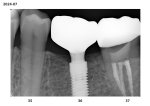

compare01.jpg

compare02.jpg

Я поставил брекеты в 35, носил 2 года.

По баблу вышло 200 брекеты, 120 пломбы, 300 два импланта и 3 коронки.

Ровного зубного ряда не получилось нихуя. Есть некоторые проблемы с балансом нагрузки лево\право. Виноват в этом ортодонт или ортопед, хуй знает.

Что могу посоветовать - иди к топам. В подвальных клиниках могут сделать хуево. Тут как повезет. Я ходил в среднюю несетевую клинику. Имея теперь возможность сравнивать, думаю скорее по классу это была нижне-среднего уровня лечебня, так как фотопротоколами или коффедрамом они себя не утруждали. С другой стороны, и какого-то явного пиздеца не было.

Локация - новая москва.